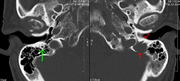

The diagnostic examination of a person with suspected multiple myeloma typically includes a skeletal survey. This is a series of X-rays of the skull, axial skeleton, and proximal long bones. Myeloma activity sometimes appears as "lytic lesions" (with local disappearance of normal bone due to resorption) or as "punched-out lesions" on the skull X-ray ("raindrop skull"). Lesions may also be sclerotic, which is seen as radiodense.[70] Overall, the radiodensity of myeloma is between −30 and 120 Hounsfield units (HU).[71] Magnetic resonance imaging is more sensitive than simple X-rays in the detection of lytic lesions, and may supersede a skeletal survey, especially when vertebral disease is suspected. Occasionally, a CT scan is performed to measure the size of soft-tissue plasmacytomas. Nuclear Medicine Bone scans are typically not of any additional value in the workup of people with myeloma (no new bone formation; lytic lesions not well visualized on nuclear bone scan).

A CT of the brain revealed a lytic lesion in the left temporal bone (right side of image), and petrous temporal bones involving the mastoid segment of the facial nerve canal. Red arrows: lesion; green arrow: normal contralateral facial nerve canal. The lesions are consistent with a myeloma deposit.

CT scan of the lower vertebral column in a man with multiple myeloma, showing multiple osteoblastic lesions: These are more radiodense (brighter in this image) than the surrounding cancellous bone, in contrast to osteolytic lesions, which are less radiodense.